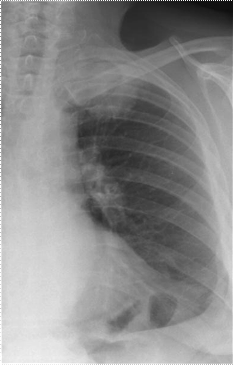

К периферическому раку относятся также верхушечный (Приложение А рисунок 6) и кортикоплевральный рак, имеющие характерные клинико-рентгенологические проявления.

Верхушечный рак легкого (опухоль Пэнкоста).

В современном понимании - это стелющийся периферический рак I сегмента легкого, прорастающий окружающие ткани, приводящий к разрушению I, II, иногда III ребер и верхних грудных позвонков.

В начале заболевания клиническая картина скудна и проявляется болями в верхней конечности без других неврологических симптомов, что приводит к диагностическим ошибкам и безуспешному лечению по поводу плексита или бурсита.

Рентгенологическая картина опухоли Пэнкоста в этот период также не характерна. В некоторых случаях отмечается лишь понижение прозрачности верхушки легкого, в других - малоинфонсивная плоская тень без четких контуров, симулирующая апикальные плевральные наложения.

На определенном этапе роста опухоли нижний край затемнения на верхушке становится более четким, а сама тень более интенсивной и оформленной. Изменения со стороны ребер не выявляются. Клинически отмечаются нарастающие боли в верхней конечности и грудной клетке.

Для уточнения характера поражения у больных с такой клинико-рентгенологической картиной необходимо использовать томографию (Приложение А рисунок 7).

В дальнейшем опухоль прорастает ребра, позвонки, плечевое сплетение. Сдавление подключичных сосудов может вызвать отек конечности, при поражении пограничного симпатического ствола развивается синдром Горнера - птоз, энофтальм, миоз.

В этой стадии заболевания на рентгенограммах выявляется интенсивное затемнение верхушки легкого с дугообразной нижней границей. Очертания верхней части тени четко не выявляются. Определяется разрушение IIII ребер - от узурации небольших участков до полной деструкции на большом протяжении, а также поражение боковых поверхностей тел и поперечных отростков позвонков.

Важно подчеркнуть, что при наличии интенсивного затемнения верхушек легких, необходимо тщательно изучать состояние ребер, особенно их задних отрезков.